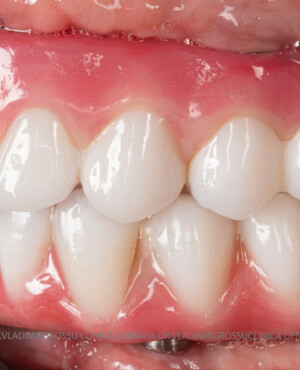

- Posibilitatea realizării unei proteze cu 12-14 dinți, oferind un aspect estetic natural și funcționalitate optimă.

Pentru pacienții cu edentație extinsă sau dinți nefuncționali, metoda All-on-6 oferă o alternativă modernă și eficientă la proteza mobilă, asigurând o restaurare fixă, stabilă și estetică a danturii. Datorită distribuirii optime a implanturilor și a tehnologiei avansate implicate, această soluție îmbunătățește considerabil calitatea vieții, confortul și funcționalitatea orală. Succesul tratamentului depinde de o planificare riguroasă, de utilizarea componentelor de calitate și de competența echipei medicale, ceea ce face ca alegerea unei clinici specializate să fie esențială pentru obținerea unor rezultate durabile și sigure.